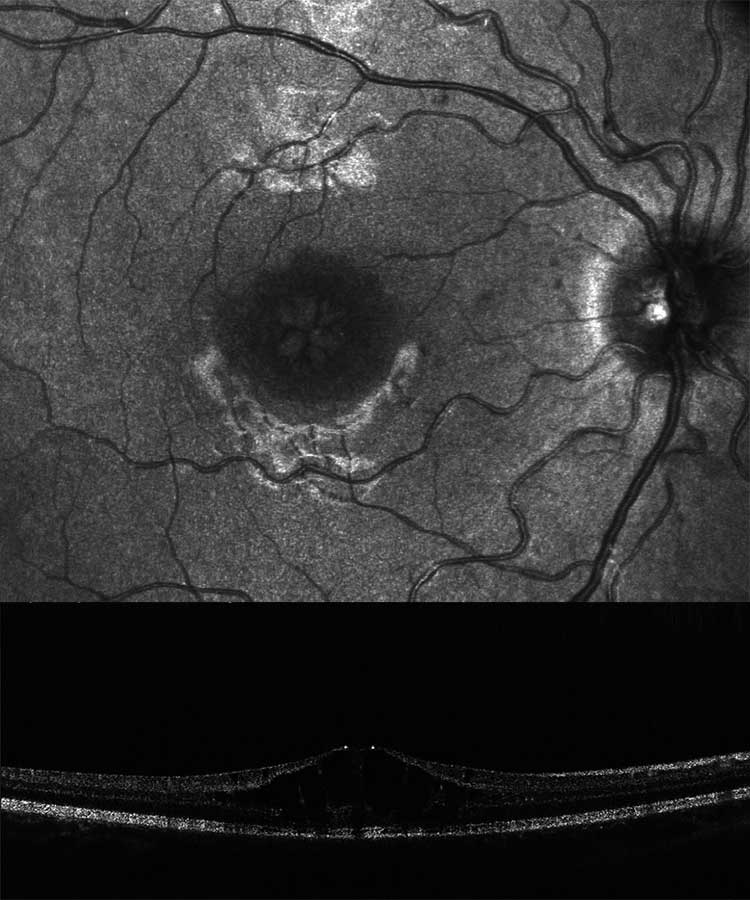

A 78-year-old patient came to the clinic for the first time and reported a visual change that had existed since childhood, and which had not been further clarified so far. The primary reason for coming was a visual defect of his 8-year-old grandson, which had now also been diagnosed. The visual acuity of the index patient was 0.3 on the right and 0.2 on the left eye. Funduscopic examination in mydriasis revealed bilateral diffuse pigment epithelial dystrophy and atrophy of the central and peripheral retina with no preference for one or the other area and no abnormal optic disc findings. Optical coherence tomography of the central retina showed foveal atrophy on both sides with indistinct retinal layers and single cystoid structures as well as unspecific atrophy mainly of the nerve fibre layer, the ganglion cell layer and the photoreceptors of the foveola. In addition, an atypical epiretinal gliosis and an unusual separation of retinal tissue in the area of the internal limiting membrane and the nerve fibre layer were seen (Figure 1).

No clear diagnosis of retinal dystrophy could be assigned to these unspecific changes after the initial examination. In a further consultation, the grandson was clinically examined with a visual acuity of 0.2 on the right and 0.3 on the left and a photographically documented star pattern of the macula on funduscopy (Figure 2a). We could not find a pigment epithelial dystrophy as seen in the grandfather and the optic disc findings were unremarkable. On OCT examination of the grandson‘s foveola, we found a typical splitting of the intraretinal nerve fibre layers in the sense of a foveal retinoschisis without signs of a peripheral retinoschisis (Figure 2b). The mother of the child (daughter of the index patient) was ophthalmologically healthy with a visual acuity of right/left 1.0 and unremarkable OCT findings. Other family members were not affected (genealogy, Figure 3). The family was examined at the human genetics consultation, where a panel diagnosis (Sanger sequencing, panel macular dystrophy) was initiated in the index patient and the affected grandchild, based on the course in the grandfather, the clinical findings in the child and the inheritance derived from the genealogical analysis (X-linked recessive) with the suspected diagnosis of X-linked juvenile retinoschisis.